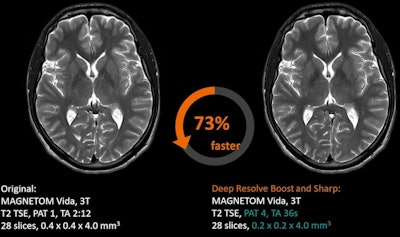

Deep Resolve Boost for MRI reconstructions, Siemens Healthineers

Deep Resolve Boost is a k-space-based reconstruction protocol that focuses on artifact reduction. It is a recent addition to the Deep Resolve AI-based reconstruction protocol for MRI, which was first introduced at RSNA 2020.

Deep Resolve Boost enables users to acquire MRI exams with shorter time periods, such as a 15-second knee exam, with images then boosted to full image quality using the protocol, according to Siemens. Another protocol, Deep Resolve Swift Brain, enables a brain scan to be performed in less than two minutes.

Deep Resolve Boost is applicable from head to toe, and the "denoising strength" can be adapted by choosing from three levels. It can be combined with Deep Resolve Sharp and SMS TSE, rendering this the first k-space-to-image-space deep learning reconstruction that can be combined with simultaneous multi-slice turbo spin echo (TSE) imaging, the vendor claims.

"Image quality in standard 2D MRI sequences, accelerated in simulation beyond the threshold of standard acceptable noise levels, can be substantially improved by applying an iterative denoising algorithm using supplementary information about the image noise level," stated Dr. Johan Dehem, from Jan Yperman Ziekenhuis, Ypres, Belgium, in a Siemens-supported article about initial clinical experiences of the technology.

The software is available on the Magnetom Lumina, Magnetom Vida, Magnetom Vida Fit, Magnetom Altea, Magnetom Sola, and Magnetom Sola Fit. The minimum software version required is the Syngo MR XA50A and Syngo MR XA51A. Additional technical prerequisites may apply, stated the vendor.